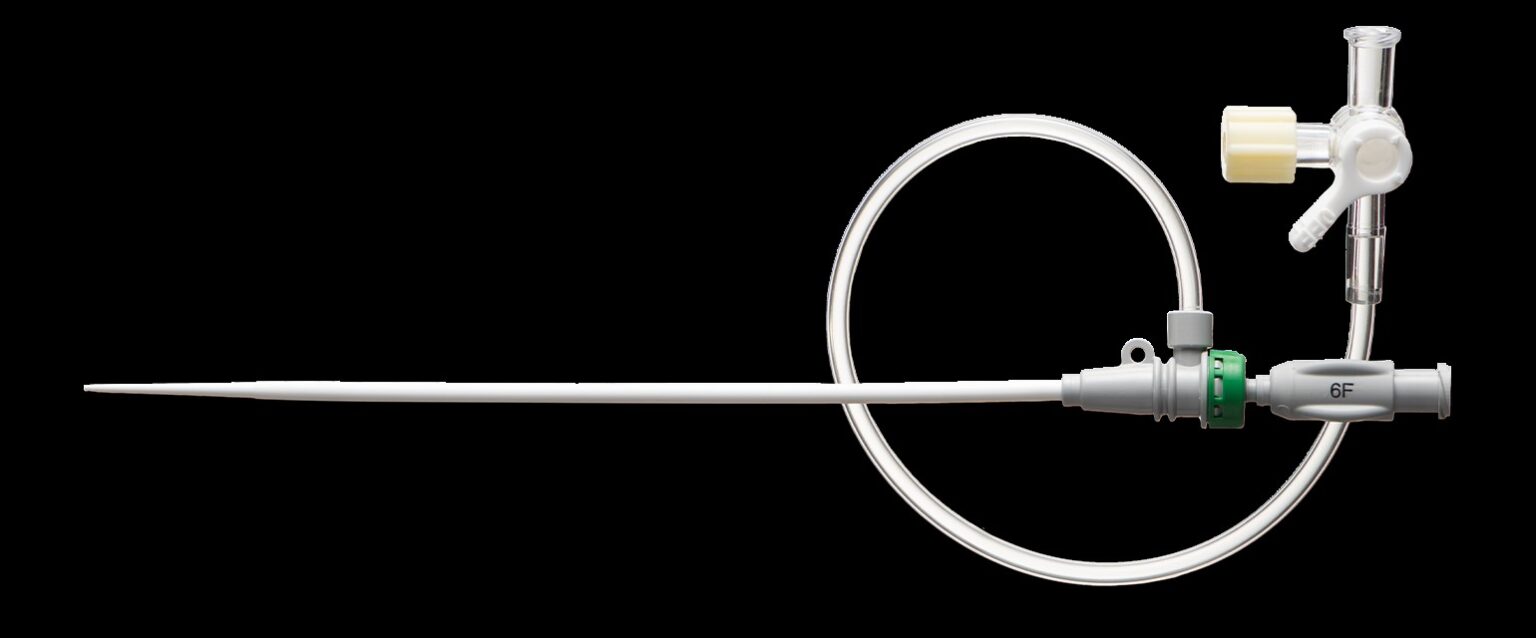

Silicone Medical Radial Introducer Kit, 7 Fr, 2.75" Length, HV Radial with Dilator and Guidewire

| OD (in) | 0.091 |

|---|---|

| Length (in) | 2.75 |

| DIS Type | Radial Introducer Kit |

| French Size | 7 |

| Coating | Silicone |

| Guidewire | 0.035" x 50 cm SS Core/SS Tip |

| Tip Shape | J Tip |

| Packaging | 1/bag |

This high-volume radial introducer kit includes a 7 Fr, 2.76 inches sheath, a 12.6 cm dilator, a 0.018″ x 45 cm guidewire with nitinol core and gold coil, and a 21G x 2.5 cm needle. The sheath features a hydrophilic coating for smooth insertion and kink resistance, while the guidewire offers enhanced radiopacity for precise navigation. Designed for radial access procedures, the kit supports high-flow applications and minimizes vessel trauma. Components are supplied in sterile packaging compliant with ISO 10993 standards. The integrated dilator and guidewire facilitate straightforward micropuncture techniques. This configuration is suitable for interventional cardiology and vascular access procedures requiring reliable radial introducer systems.